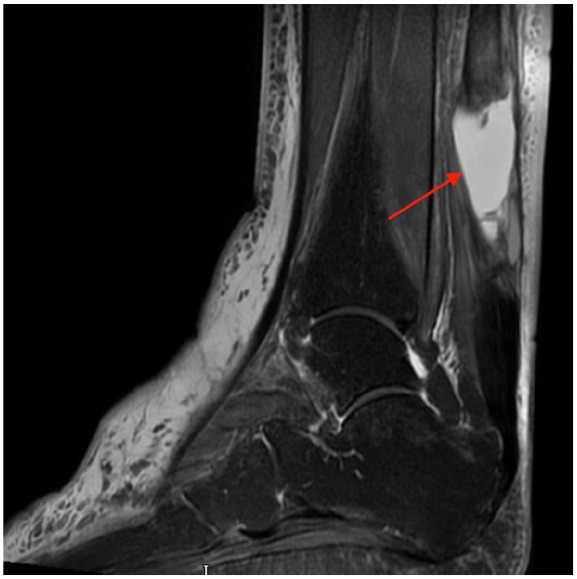

Abstract Image